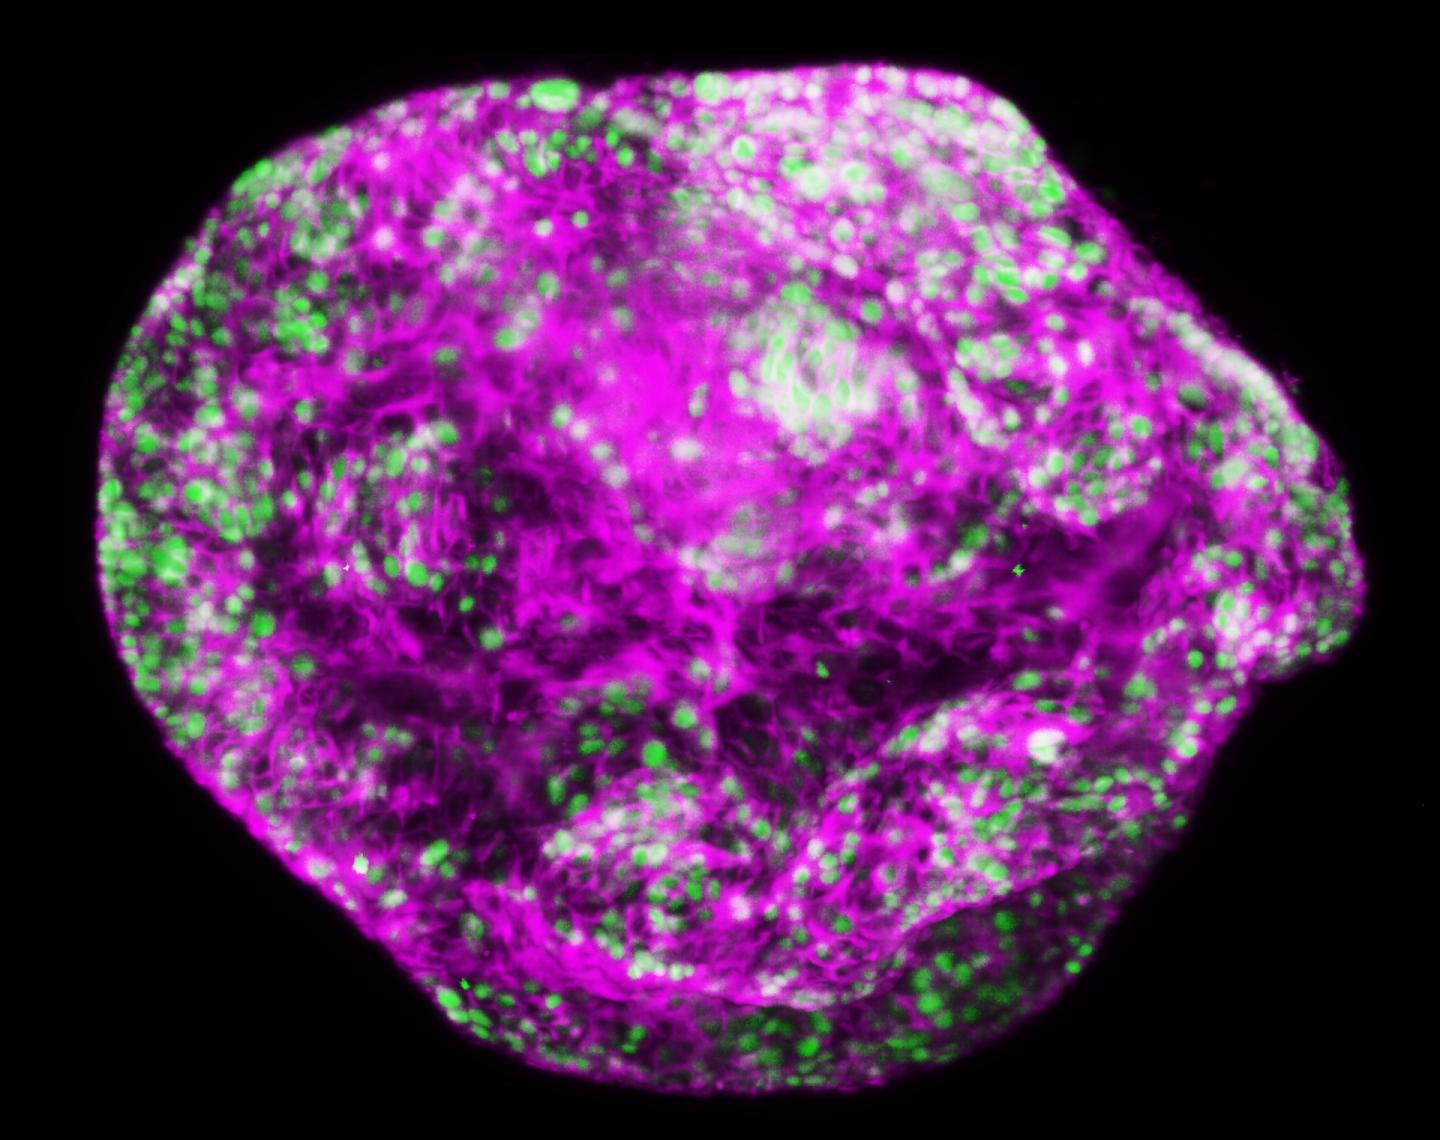

Melbourne researchers have made the surprise discovery that the 'odd one out' in a family of proteins known to drive cancer development is instead critical for preventing stomach cancers.

The research team showed switching off a gene called NF-κB1 caused spontaneous development of stomach cancers, driven by chronic inflammation. The study also revealed that immunotherapy may prove to be a significant tool for treating stomach cancers that are driven by runaway inflammation, warranting further investigation.

"Stomach cancer is a disease where immunotherapy is still in its infancy. This is the first preclinical model of stomach cancer that repeats the pattern of human stomach cancer development, that involves progression from chronic stomach inflammation through to fully invasive cancer," Dr Putoczki said.